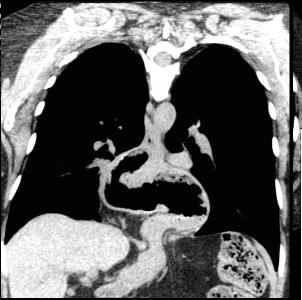

Meme cas en coupe frontale (

coronale ) .Le cardia et une partie de estoma

situent au dessus le diapragme . Image du

coupe est si nette |